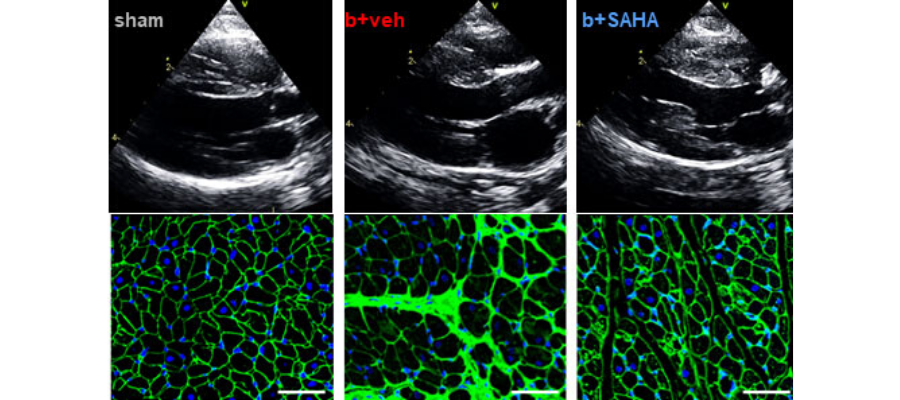

First row: Representative echocardiography images showing left ventricle wall thickness and left atrium size.

Second row: Cross-sectional tissue sections stained with wheat-germ agglutiin (WGA) and DAPI. WGA stains the border of the cardiomyocytes green and DAPI stains the nucleus blue.

Following treatment with SAHA, HFpEF animals showed amazing improvements. In particular, hypertrophy of the left ventricle was significantly reduced in treated compared to untreated animals. The left ventricle was also much more relaxed in treated animals, enabling the heart to fill and pump more effectively and leading to overall improvements in heart structure and function.

The Houser and McKinsey teams tested SAHA in an HFpEF model in which animals progressively developed typical signs of disease, including loss of exercise tolerance and shortness of breath. The animals also experienced tissue changes similar to those that occur in humans with HFpEF, most notably heart remodeling. Heart remodeling in HFpEF characteristically involves hypertrophy, or enlargement and thickening, of the left ventricle, which is the main pump that pushes oxygen-rich blood into the aorta and through the body. Hypertrophy is one way the heart attempts to respond to chronic cardiovascular problems, such as high blood pressure.